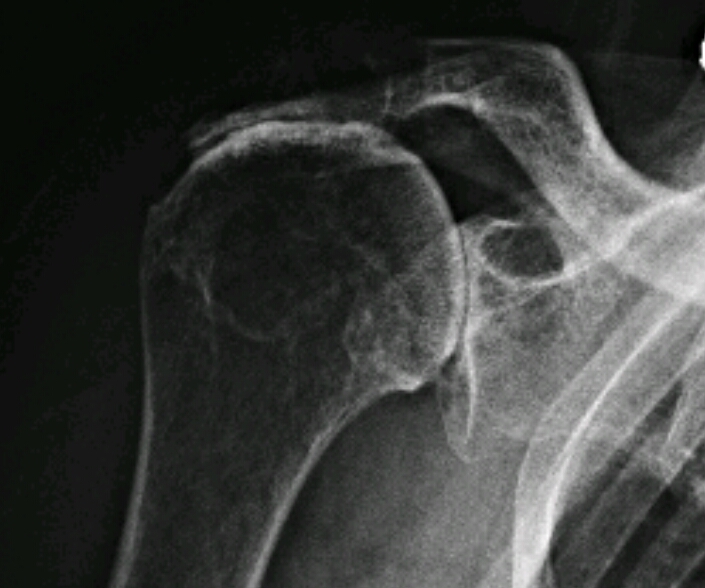

What disease is this? What features make the diagnosis?

Rotator cuff arthropathy

cystic changes

superior migration of humerus due to unopposed deltoid

erosions at acromion